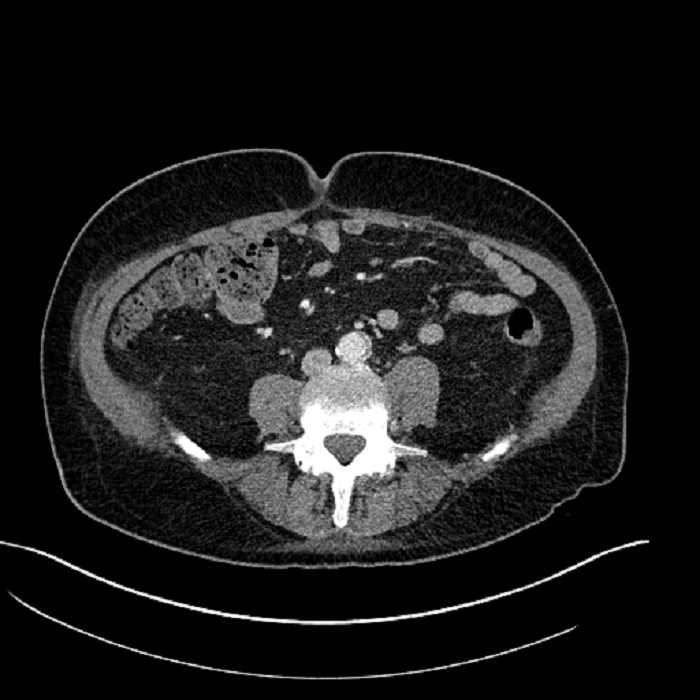

Age: 63

Sex: Male

Indication: Abdominal pain

• Large fluid density structure in hepatic segments 7 and 8 measuring 10 x 7 x 7 cm with internal septation and circumferential ill-defined low density compatible with edema

• Peripherally enhancing subcapsular collections along the anterior margin of the left hepatic lobe measuring 3 x 1 cm and 2 x 1 cm

• Clearly marginated fluid density structure in segment 7 and several other scattered tiny hypodensities, which likely represent cysts

• Hepatic abscess

Acute sigmoid diverticulitis complicated by a small contained perforation and a large abscess in the right hepatic lobe. Additional small subcapsular abscesses along the anterior margin of the left hepatic lobe.

• The classic CT imaging appearance is a double target sign with internal low density surrounded by an internal enhancing rim (capsule) and a low density external rim (edema)

Hepatic abscess showing the double target sign with low density internally surrounded by a thin inner enhancing rim (red arrow) and ill-defined outer low density rim (yellow arrow). Blue arrow indicates an internal septation. Red arrows: additional smaller subcapsular abscesses. Red arrow: focal contained perforation associated with diverticulitis.